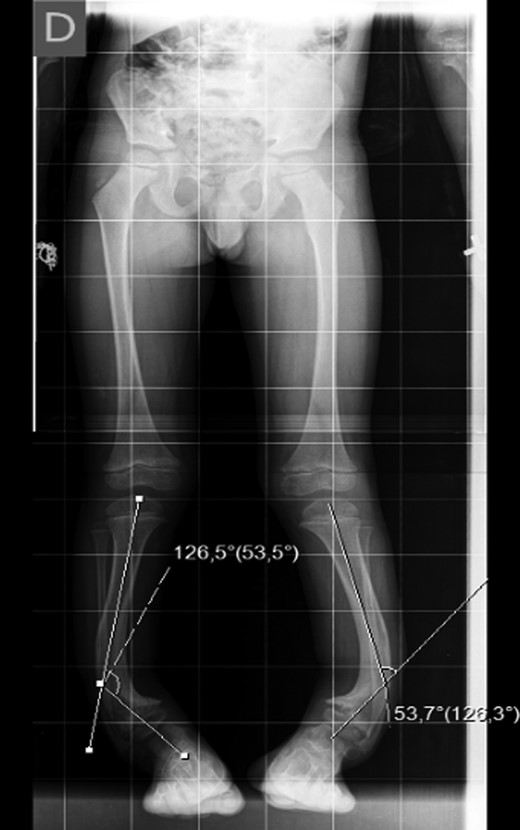

The X-ray showed a bowing of distal tibia, bilaterally, producing a varus deformity of 53 degrees (Fig. 2).